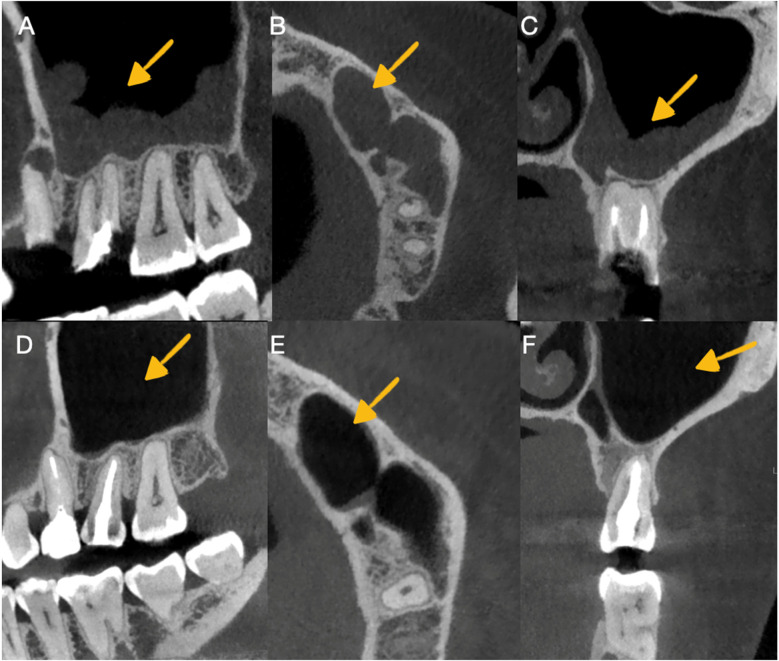

本病例报告介绍了牙齿自体移植的使用,这是一种将供体牙齿转移到同一患者的受体部位的手术,改善了功能和美学特征。与传统的修复和外科治疗(如牙种植)相比,该技术的优点被讨论。患者27岁,无相关病史,因牙髓治疗和牙源性鼻窦炎导致的骨折牙疼痛和不适进行评估。诊断出不可修复的上颌第一磨牙并拔出并替换为先前经根管治疗的上颌第三磨牙,使用3d打印复制品重塑牙槽部位。干预是成功的,之后进行了充分的临床和影像学随访3年,显示良好的骨形成和牙周韧带的连续性,没有病理性吸收的迹象。这个案例表明,如果计划和执行得当,牙齿自体移植可以成为一种有效的、生物的牙齿康复替代方法,特别是使用先进的技术,如锥体束计算机断层扫描和3d打印供牙复制品。

This case report presents the use of dental autotransplantation, a procedure in which a donor tooth is transferred to a recipient site in the same patient, improving functional and esthetic characteristics. The advantages of this technique compared to conventional prostheses and surgical treatments, such as dental implants, are discussed. A 27-year-old patient with no relevant medical history was evaluated for pain and discomfort in fractured teeth with previous endodontic treatments and odontogenic sinusitis. A non-restorable maxillary first molar was diagnosed and extracted and replaced with a previously endodontically treated maxillary third molar, for which a 3D-printed replica was used to reshape the alveolar site. The intervention was successful, after which an adequate clinical and radiographic follow-up was carried out for 3 years, showing good bone formation and continuity of the periodontal ligament, with no signs of pathological resorption. This case demonstrates that, when properly planned and executed, dental autotransplantation can be an effective and biological alternative for dental rehabilitation, especially with the use of advanced technologies, such as cone beam computed tomography and 3D-printed replicas of donor teeth.